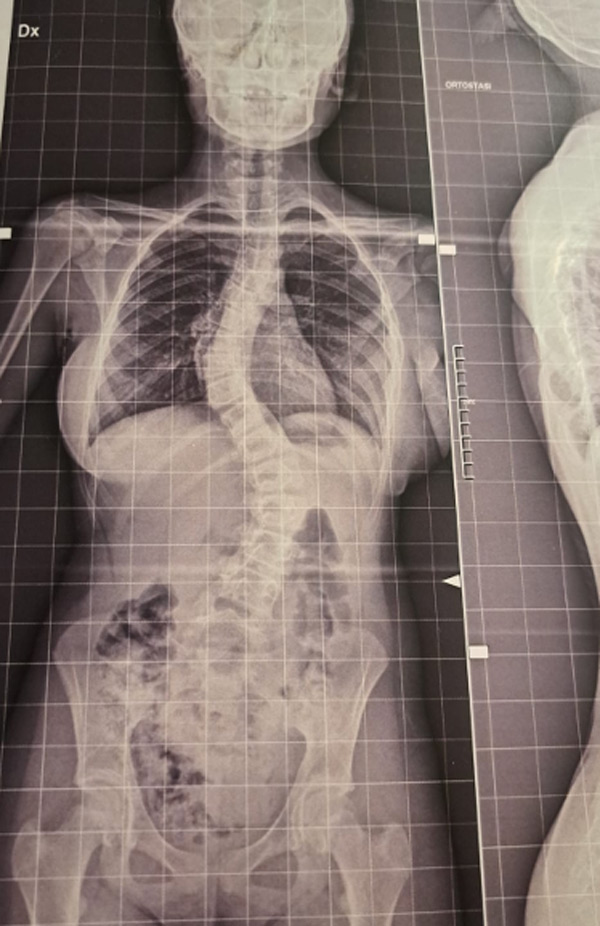

DIAGNOSI:

Scoliosi dorso lombare

Radiografia della colonna in toto pre-operatoria